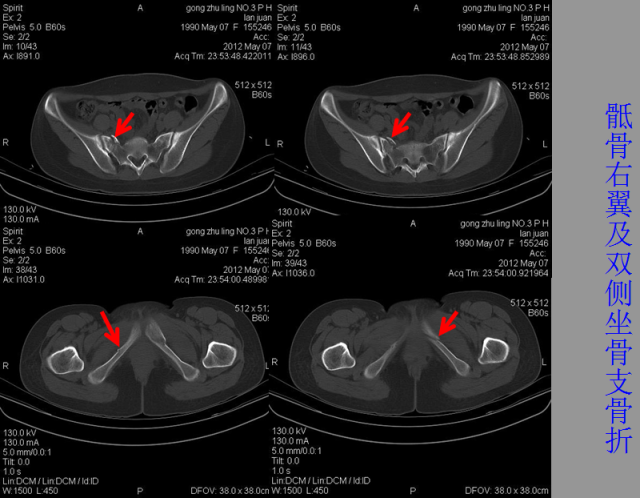

骨折篇

定义:骨折{Fracture}是指骨的完整性和连续性的折裂或粉碎。包括创伤性骨折、疲劳性骨折和病例理性骨折。 临床上以创伤性骨折*常见。